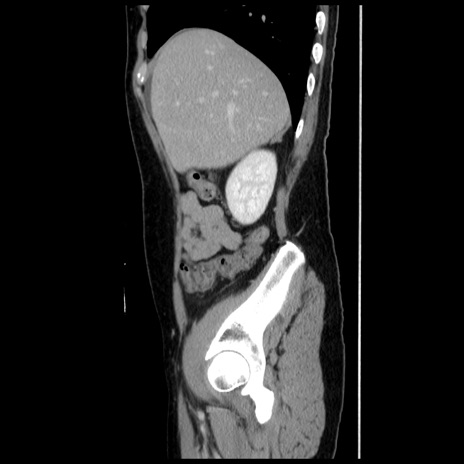

横断像

【症例】 50歳代女性

【主訴】 腹痛

【現病歴】前日生レバーを食べた。今朝に排便あり。 昼前に突然発症の腹痛を生じ、当院救急外来を受診した。

【既往歴】 子宮筋腫にてで子宮全摘後

【身体所見】 意識清明、腹部:平坦、軟、下腹部やや左を中心に圧痛・反跳痛あり、筋性防御あり

【データ】WBC 7800、CRP 0.07